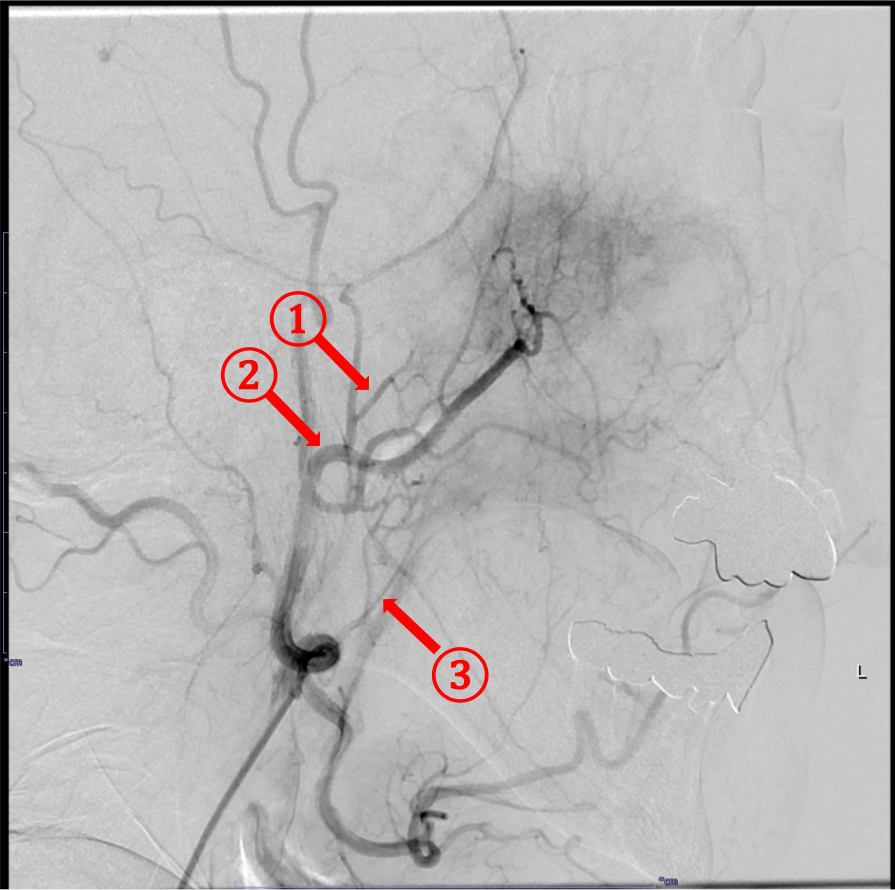

RADPLATは大量シスプラチンの超選択的動注化学療法と放射線治療の同時併用療法であり、局所制御の向上と臓器機能温存を期待できる。超選択的動注化学療法で癌の根治を目指す上で、腫瘍の進展範囲や栄養血管の同定、また周囲の重要構造物との関係やアクセスルートなど詳細な術前評価が不可欠であり、造影CTで解剖学的構造物を正確に描出することが求められる。

当院では撮像されたCT画像を元に3D画像解析システム「SYNAPSE VINCENT」を使用して治療対象となる血管を抽出し、ワークステーション上で支援画像を作成している。これにより直感的な解剖の理解を得られるだけでなく、放射線技師や看護師など手技に関わるスタッフと事前に情報共有することが容易になり、これもまた治療の有効性や安全性を高めることに寄与する。

画像再構成は腫瘍の位置や血管走行を詳細に評価するため、0.5mmにスライス厚を設定する。各動脈、腫瘍を色分けしたVR像なども血管造影の際の支援画像として重要である。